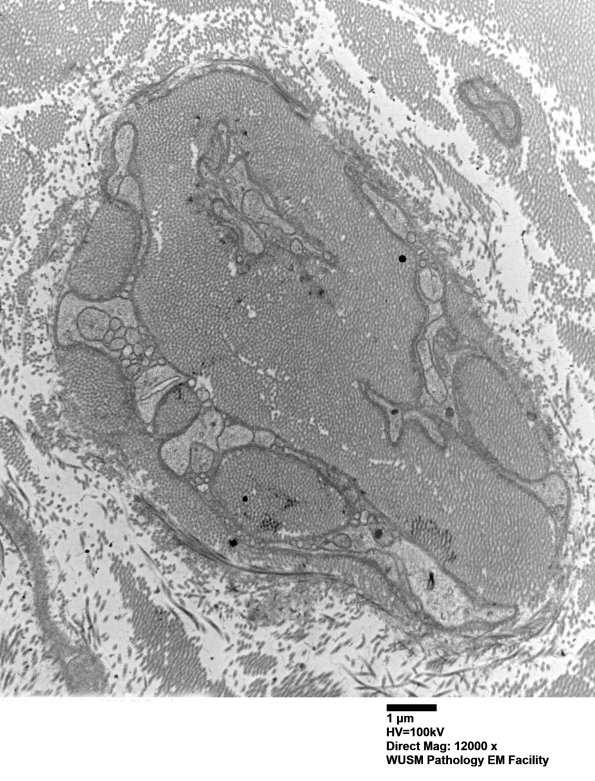

Washington University Experience | PERIPHERAL NEUROPATHY | 4 AXONAL DEGENERATION | 3 Electron Microscopy | 7A6A Chronic Degeneration (Case 33) Sural_054 - Copy

7A6A-C In this collection of processes and collagen it appears most processes are Schwannian in origin. (electron micrographs)